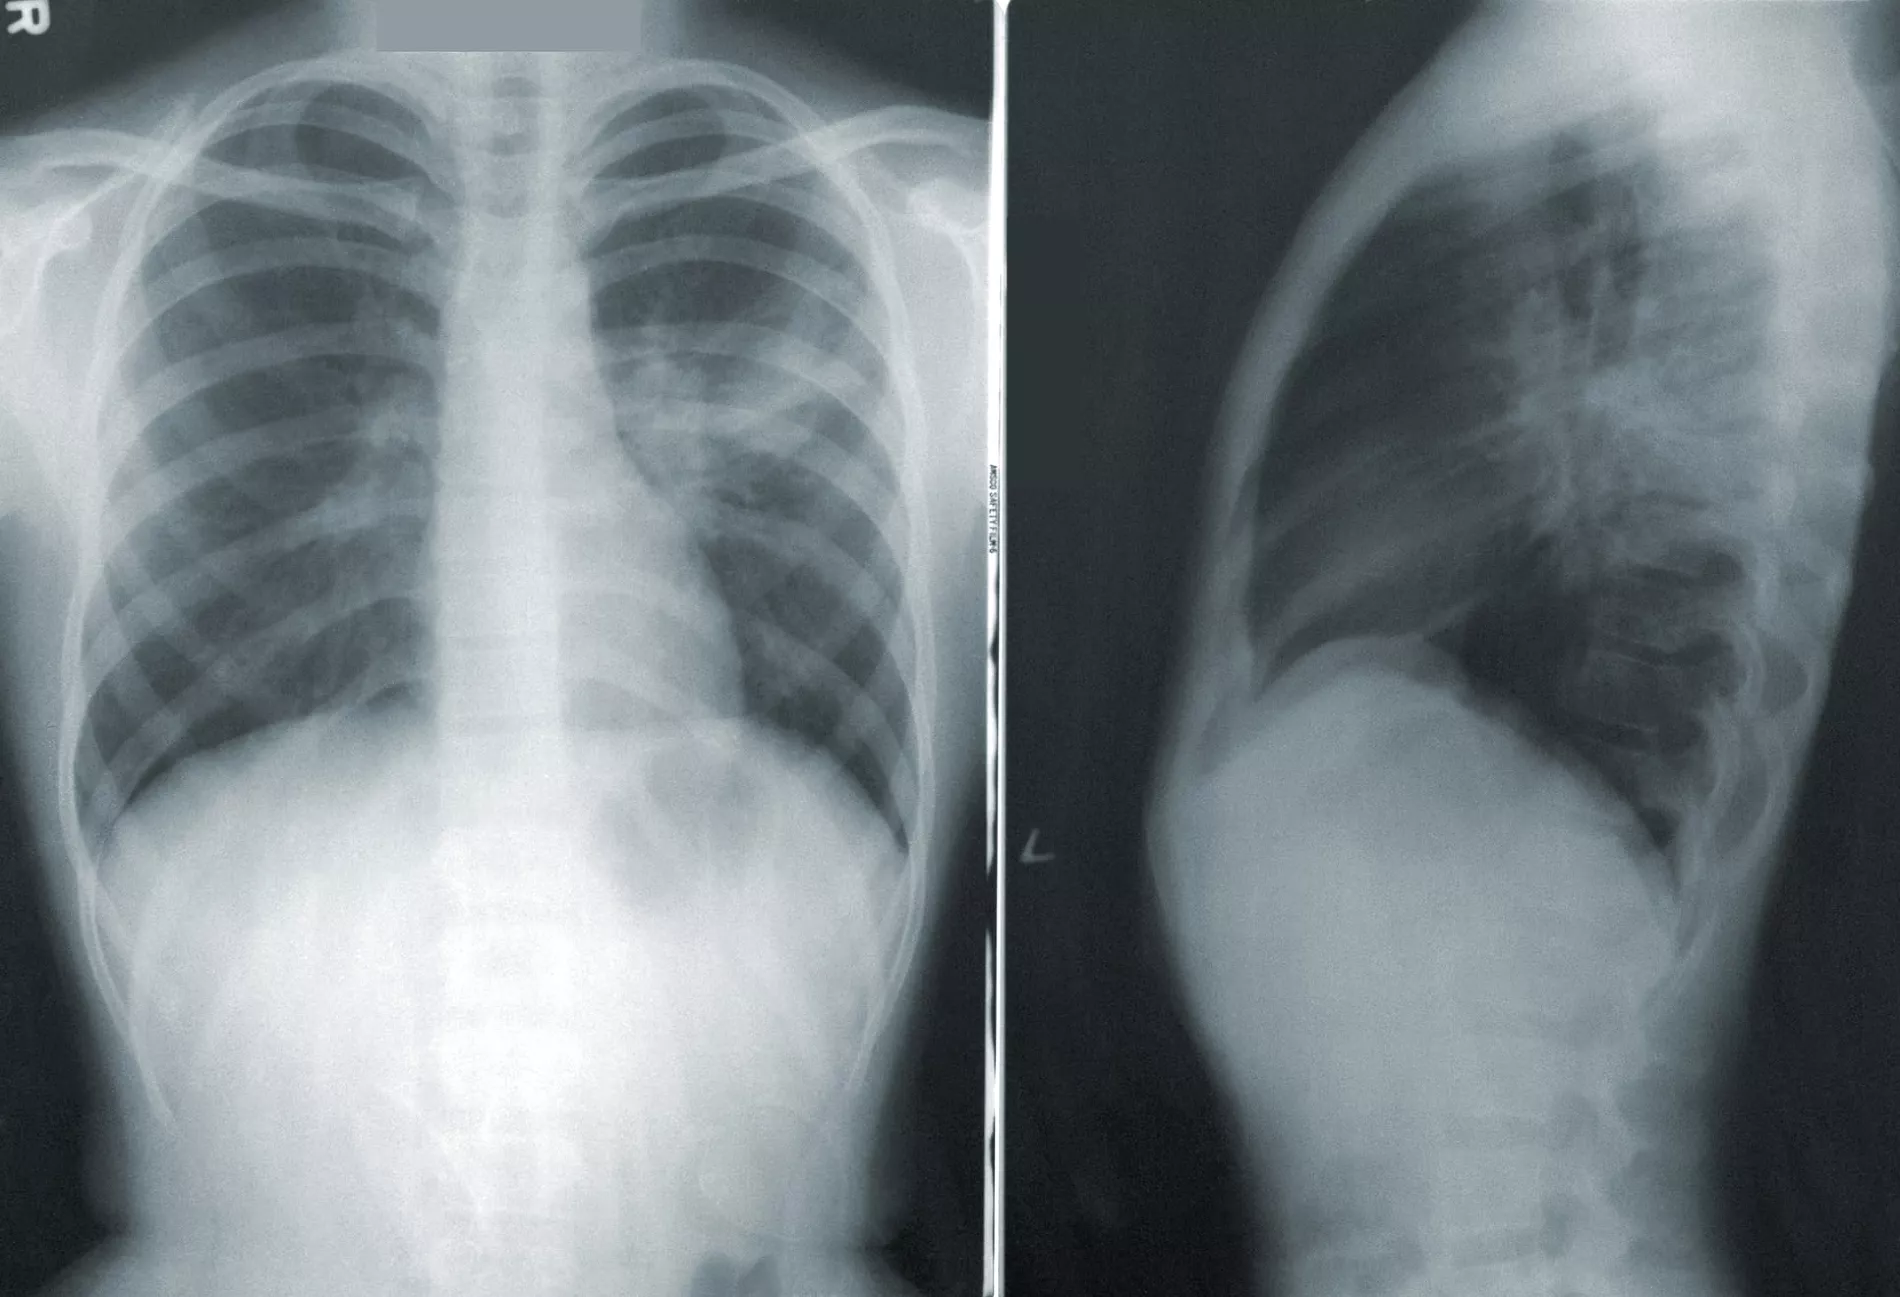

• Пневмония на рентгеновском снимке © Фото CDC (Center for Disease Control and Prevention), unsplash.com

Пневмония на рентгеновском снимке © Фото CDC (Center for Disease Control and Prevention), unsplash.com